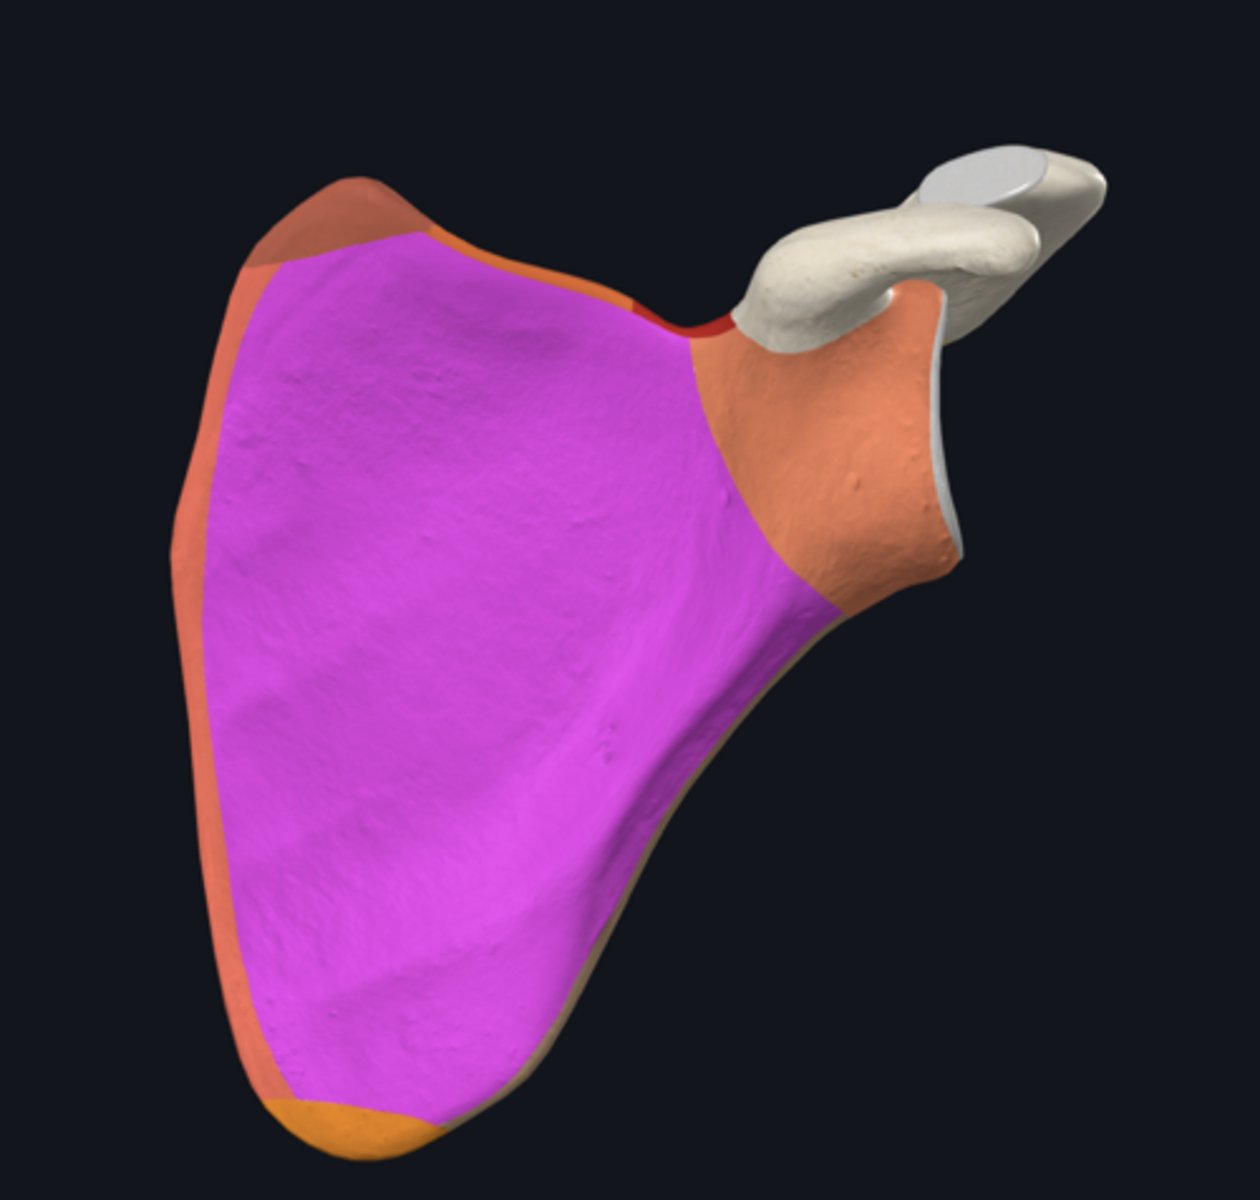

Acromion

Coracoid process

costal surface of scapula

lateral angle of scapula

posterior surface of scapula

glenoid fossa

infraglenoid tubercle

infraspinous fossa

subscapular fossa

supraglenoid tubercle

supraspinous fossa